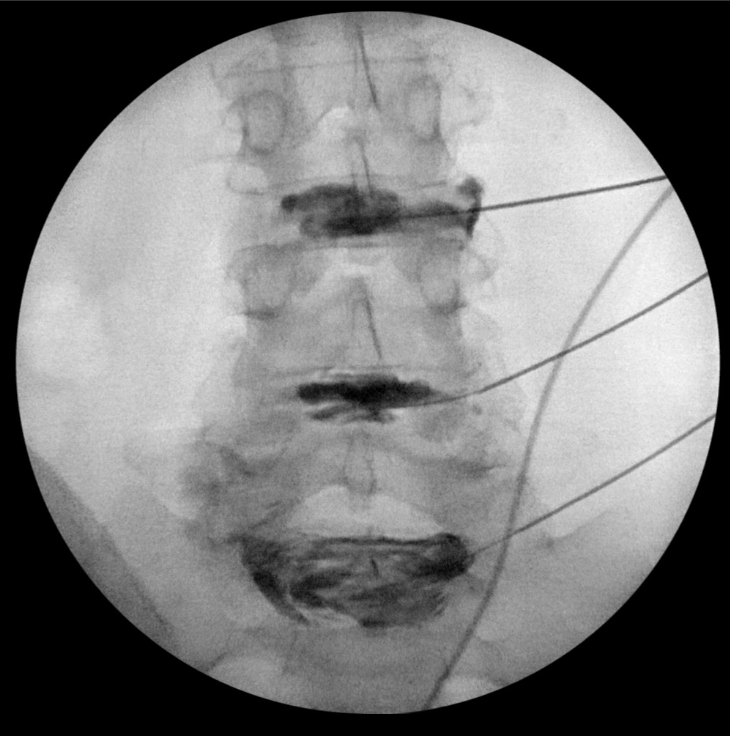

در این تست تشخیصی، رنگ کنتراست به دیسک(های) ستون فقرات که گمان می رود منبع کمردرد شما باشد، تزریق می شود. ابتدا پوست و بافت های عمیق تر با یک بی حس کننده موضعی بی حس می شوند. سپس با استفاده از هدایت فلوروسکوپی (اشعه ایکس)، یک سوزن به دیسک وارد می شود. رنگ کنتراست تزریق می شود و نظارت دقیق بر الگوی جریان رنگ و پاسخ درد شما ثبت می شود.